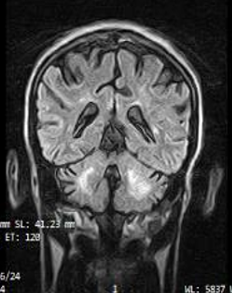

Neuroinfectious Diseases | Sep 10, 2025

Cerebral Toxoplasmosis in an HIV-Positive 32-Year-Old Male with Poor Antiretroviral Therapy Compliance

Patel Nirali Kirankumar, et al.

Cerebral toxoplasmosis is a potentially fatal infectious disease of the central nervous system induced by reactivation of Toxoplasma gondii. It affects immunocompromised individuals, specifically those...Read More